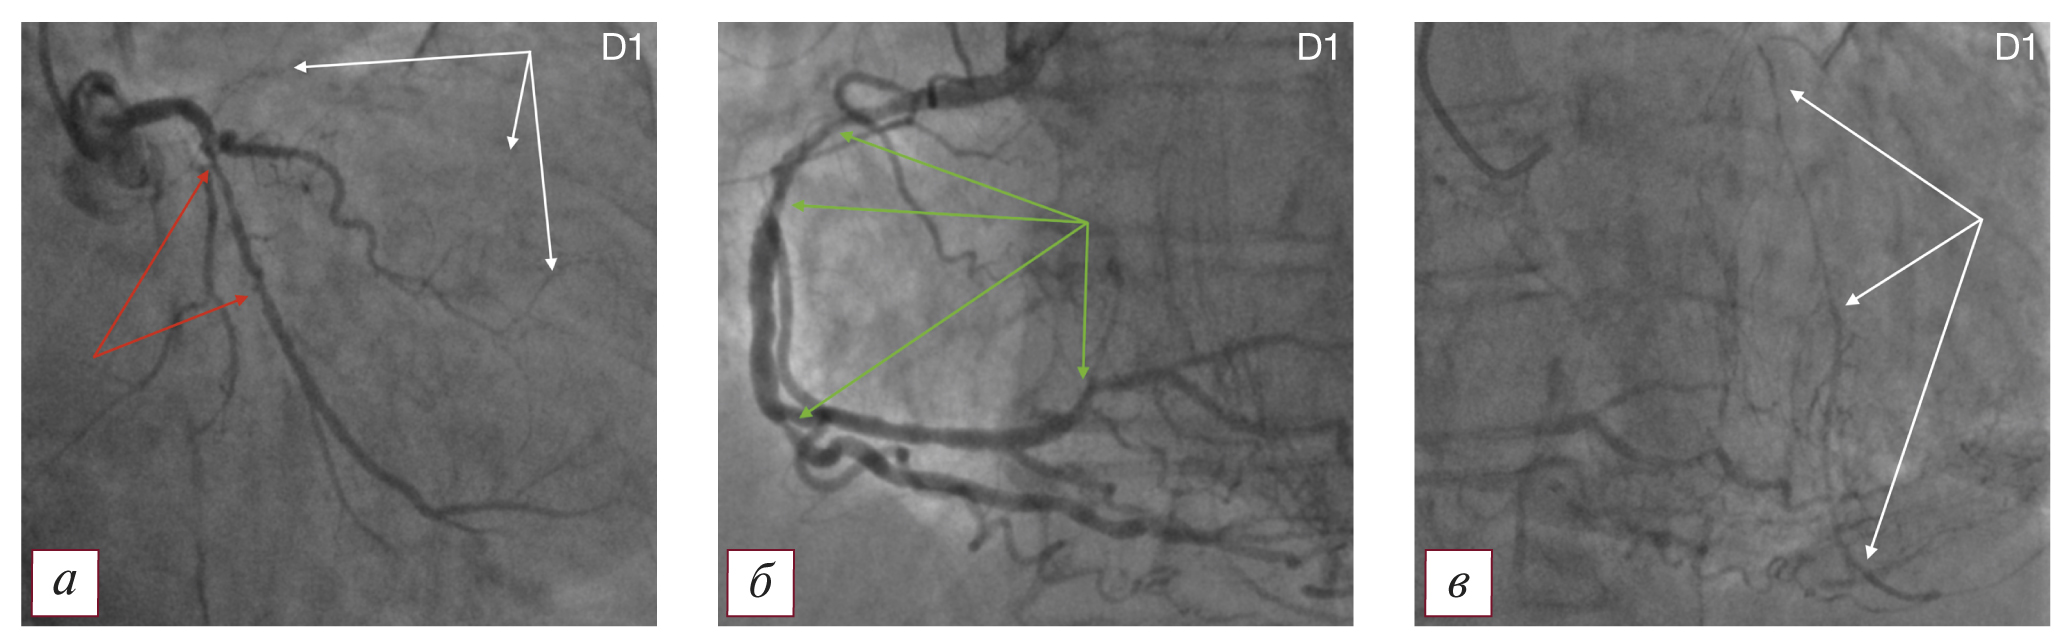

Tип D1 — ПАЛЖ и множественное гемодинамически значимое поражение крупных коронарных артерий и их ветвей при правом типе кровоснабжения миокарда. Типичная коронарографическая картина представлена на рис. 1.

Рис. 1. Коронароангиографическая картина поражения коронарного русла и постинфарктной аневризмы левого желудочка по типу D1: а — коронароангиография левой венечной артерии (белые стрелки — русло передней нисходящей артерии, окклюзированное в проксимальной трети; красные стрелки — гемодинамически значимое поражение огибающей артерии, протяженные эшелонированные стенозы до 75% огибающей артерии); б — протяженные эшелонированные стенозы до 85% проксимальной и средней части правой коронарной артерии, а также ее ветвей (указаны зелеными стрелками); в — ретроградное заполнение дистальной и средней трети передней нисходящей артерии из бассейна правой коронарной артерии, коллатеральный кровоток Rentrop III (указано белыми стрелками). / Fig. 1. Coronary angiographic picture of lesions of the coronary bed and postinfarction aneurysm of the left ventricle according to type D1: a — coronary angiography of the left coronary artery (white arrows — the bed of the anterior descending artery occluded in the proximal third; red arrows — hemodynamically significant lesion of the envelope artery, extended echeloned stenoses up to 75% of the envelope artery); б — extended echeloned stenoses up to 85% of the proximal and middle parts of the right coronary artery, as well as its branches (indicated by green arrows); в — retrograde filling of the distal and middle third of the anterior descending artery from the basin of the right coronary artery, collateral blood flow Rentrop III (indicated by white arrows).